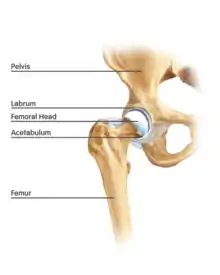

Anatomy

The hip is essentially a ball and socket joint. It consists of the head of the femur (the ball) and the acetabulum (the socket). Both the ball and socket are congruous and covered with hyaline (or articular) cartilage, which allows smooth, almost frictionless gliding between the two surfaces. The edge of the acetabulum is surrounded by the acetabular labrum, a fibrous structure that envelops the femoral head. (See fig. 1) The labrum acts as a seal, or gasket, around the femoral head. However, this is not its only function, as it has been shown to contain nerve endings, which may cause pain if damaged.[18] The blood supply of the labrum has also been demonstrated.[25] The joint itself is encompassed by a thick, fibrous joint capsule, which is lined by synovium. The ligaments that keep the hip joint in place are in fact, thickened areas of joint capsule, rather than distinct structures. The synovium generates fluid that lubricates the joint; in that fluid are the nutrients needed to keep the cartilage cells alive. A total of 27 muscles cross the hip joint, making it a very deep part of the body for arthroscopic access. This is one reason why hip arthroscopy can be quite technically demanding.